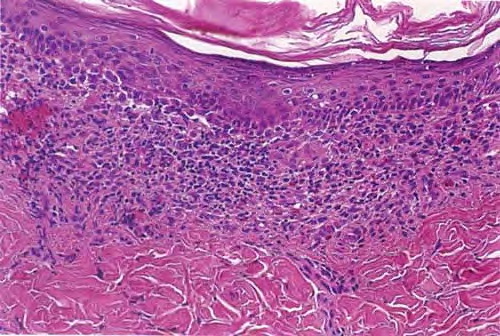

Histiocytosis X =x كثرة المنسجات